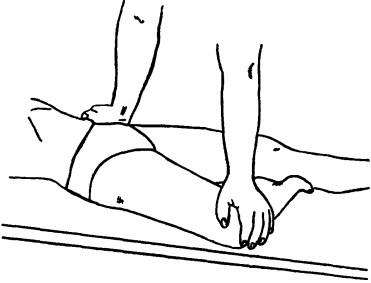

Ábra. 143. Test „szorította” Stoddart végre abban a helyzetben a beteg végre fekvő helyzetbe

Bár a sacroiliacalis együttes nem áll tapintása diagnosztizálni sikeresen alkalmazott terhelés együttes figyelemelterelés tesztek, provokáló fájdalom a fartájékba. Teszt „szorította” Stoddart jellemzi nyomásérzékenység az összenyomással elülső végei a csípőtaréj felé a középvonal a helyzetben a beteg hátán fekszik (ábra. 143), vagy az oldalsó (ábra. 144). Ez a mozgás növeli a közös réseket az ízületek. A teszt „mozgó egymástól” Stoddart jellemezve nyomásérzékenység, amikor nyomást a csípőtaréj oldalai és le ugyanazon a helyen a páciens (ábra. 145).